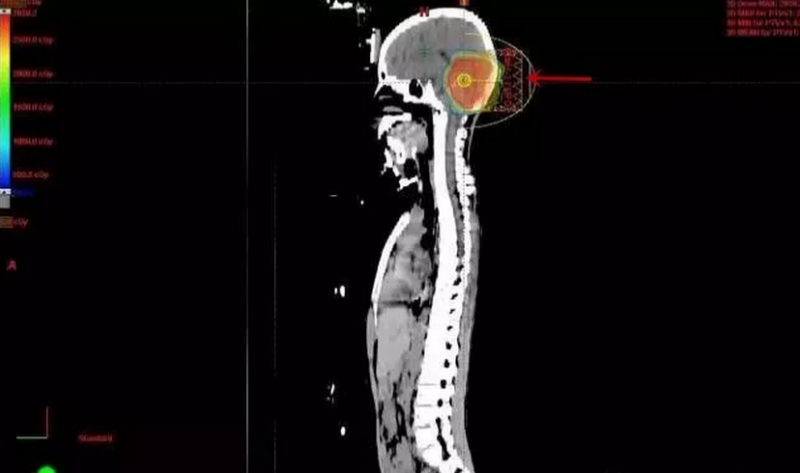

患儿发病时10岁,MR示四脑室髓母细胞瘤伴梗阻性脑积水。在国内质子治疗中心应用质子治疗行全脑全脊髓放疗28.8cGE/16次,并予后颅窝病灶局部加量24cGE/12次。后续行司莫司汀口服化疗2周期后因骨髓抑制明显未再行化疗及其他治疗。此后定期复查,现已生存13年,肿瘤未见复发,发育无畸形,身高正常。

后后颅窝肿瘤区加量质子剂量分布图:其余脑组织未受照射